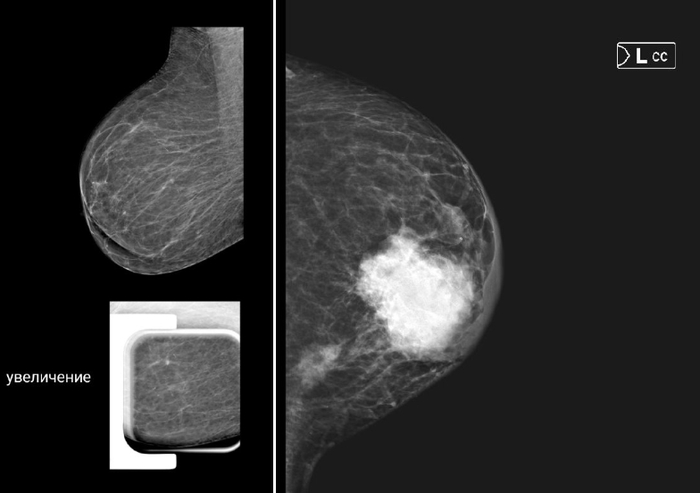

2 снимка маммографии.

На обоих рак молочной железы, но какая разная ситуация.

На 1ом снимке (1 стадия -опухоль 5 мм) болезнь почти «немая». Чаще всего это просто небольшое уплотнение в груди, которое не болит и никак не мешает жить. Его можно нащупать случайно или увидеть на маммограмме. Ни слабости, ни боли, ни изменений в самочувствии нет. Женщина может отлично себя чувствовать и даже не подозревать о проблеме.

На 2 снимке опухоль распространена в молочной железе и регионарных л/узлах (в данном случае - это 3 стадия). Организм кричит о беде. Опухоль видна визуально, отмечается уплотнение, изменение формы молочной железы, пальпируются л/узлы. Опухоль может прорастать в кожу, вызывая её изменение (симптом «лимонной корочки», покраснение, язва), или в мышцу. Но главный признак — поражение регионарных лимфоузлов в подмышечной впадине, около ключицы или грудины. Могут появиться боли, дискомфорт, отёк руки. Организм уже тратит силы на борьбу, поэтому возможны усталость и недомогание.